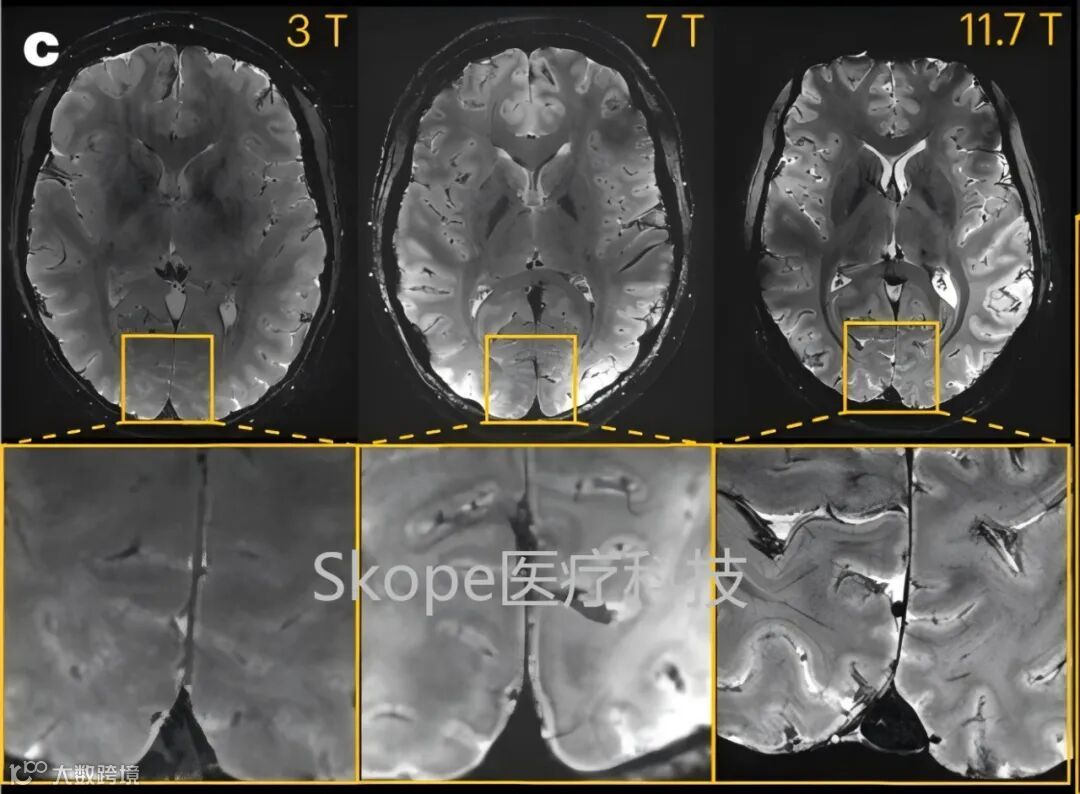

7T和11.7T下取得的T2*加权的二维梯度回波(GRE)轴向图像(不同受试者)

采集参数:分辨率=0.2×0.2×1mm³,FA=27°,TE=20ms,TR=0.6 s,带宽=40 Hz/像素,采集时间4分20秒。

这组图片直观地反映出超高场成像在图像清晰度和细节方面的显著优势。

c. 3T(左)、7T(中)和11.7 T(右)下采集的T2* 加权2D GRE轴向图像

采集时间相同(4分17秒),通过调整采集参数:3、7和11.7 T的FA(°)、TR(ms)和TE(ms)分别为27、750和45;34、950和25;27、600和20;空间分辨率:3、7和11.7 T的平面分辨率分别为0.5、0.325和0.2mm,厚度均为 1 mm来保持相似的对比度噪声比(CNR)。